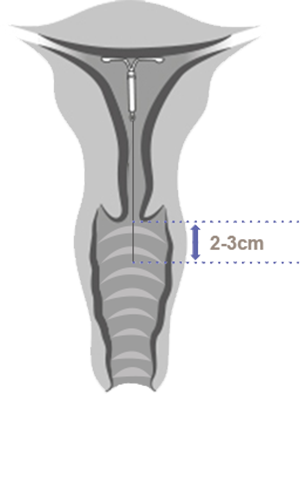

Ta ut eller bytte av Kyleena i noen få enkle trinn

Se hvordan du tar ut Kyleena

Kyleena tas ut ved å trekke forsiktig i trådene med en tang.

3 trinn for riktig uttak av Kyleena

Hormonspiralen skal tas ut innen utgangen av det femte året

Hvis kvinnen ønsker å bruke den samme metoden, kan ny hormonspiral føres inn umiddelbart etter uttak.

Hvis graviditet ikke er ønskelig, skal uttak utføres innen 7 dager etter første menstruasjonsdag, gitt at kvinnen fremdeles har en regelmessig menstruasjonssyklus.